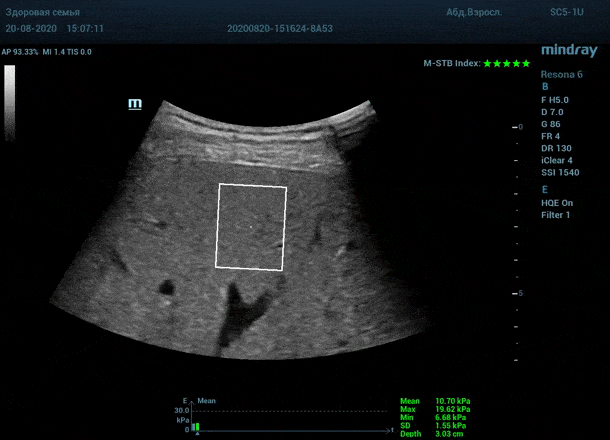

Как работает эластография сдвиговой волны? Датчик посылает плотный пучок ультразвуковых волн в ткани, ткани сжимаются, а затем возвращаются в исходное состояние за счет своей эластичности. Расправление ткани создают поперечные ультразвуковые волны, которые регистрируются трансдьюссером. Прибор во время исследования непрерывно отображает график значений плотности печени (kPa) в исследуемой зоне, достоверным считается график в виде прямой линии. Такая линия формируется путем получения близких по значению показателей. Количественным показателем является отношение межквартального интервала к медиане (IQR/Med). Допустимым считается результат с IQR/Med менее 30%. Чем данный показатель меньше, тем более точным является исследование. Для достоверного исследования в идеале нужно 10 значений.

3. - Неподвижная печень. Достигается путем задержки дыхания на выдохе. Выдох позволяет уменьшить давление на печень органами грудной клетки и брюшной полости. Задержка дыхания останавливает её. Критерием качества является индекс M-STB, выраженным в количестве звезд. Прибор определяет его автоматически. 4-5 звезд индекса свидетельствует о неподвижной печени.

Для таких сложных случаев в приборах Mindray Resona предусмотрен режим HQ Elasto. В отличии от стандартной работы эластографии HQ Elasto позволяет собрать отдельное короткое измерение в сборный график. Достаточно задержки дыхания всего в пару секунд, показатель будет записан и добавлен в график измерений. Таким образом, короткими «залпами» ультразвуковых волн по печени доктор без проблем соберет все необходимые 10 значений и проведет автоматический анализ с расчетом медианы и IQR/Med.

Приводим видео пример: использованы 3 точки доступа печени, каждое значение графика получено прицельным выстрелом HQ Elasto и собрано в единый тренд. В результате анализа 10 значений получен удивительно точный результат - статистический разброс  3.5 % IQR/Med.